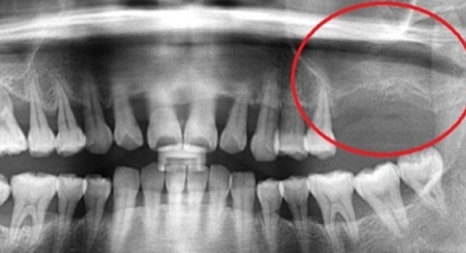

따라서, 본원은 3D CT 장비를 이용하여 육안으로 확인이 어려운

해부학적인 구조물까지 면밀히 검진한 결과를 토대로

환자분과의 충분한 상담을 통해 진료 계획을 수립합니다.

위 턱뼈는 아래턱뼈보다 얇고 코와 뺨 사이

빈 공간 (상악동)이 있어서 임플란트를 식립할 경우 실패 가능성이 높아집니다.

부족한 뼈를 보충하기 전 상악동 거상술을 시행할 때

노하우가 부족하면 임플란트 식립 후 쉽게 빠져버리거나

입 천장 쪽에 천공이 나는 부작용이 생기기 때문에

치과 진료 중 난도가 높은 과정에 속합니다.

본 환자분은 부족한 잇몸뼈를 보충하는 뼈 이식술과

난도 높은 상악동 거상술을 진행해 안정적인 목동임플란트 수술을 마쳤습니다.

연세고운미소치과 목동점 문원규 박사 (대표원장)는

턱뼈의 해부학적 구조를 충분히 고려하여 임플란트 수술을 해온 노하우를 바탕으로

상악동 거상술을 비롯한 난도 높은 수술을 안정적으로 진행하고 있습니다.